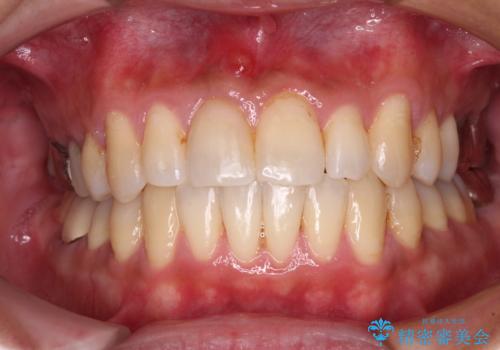

受け口傾向の咬み合わせ 前歯のデコボコをワイヤー矯正で素早く改善

前歯のクロスバイトは、改善の途中で歯髄壊死を起こすリスクが高くなるため、マウスピース矯正よりもワイヤー矯正をお勧めしております。

この患者様もクロスバイトはあっという間に改善され、1年強で速やかに治療を終えることができました。